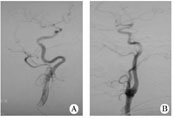

1.1對象2011-08至2012-02在我院住院的缺血性腦卒中患者,經腦血管造影篩選出年滿18周歲、頸內動脈迂曲(頸內動脈彎曲如螺旋狀或有2個或2個以上的彎曲)、而無狹窄或閉塞的患者30例(迂曲組,圖1A),無頸內動脈迂曲、狹窄或閉塞的患者30例(無迂曲組,圖1B)。所有患者在腦血管造影前均簽署手術知情同意書。

圖1患者頸內動脈血管造影

A迂曲;B無迂曲